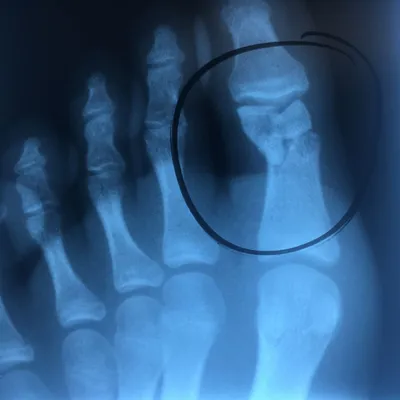

Pediatric Coalition Fracture of the DIPJ fifth toe initial and healed